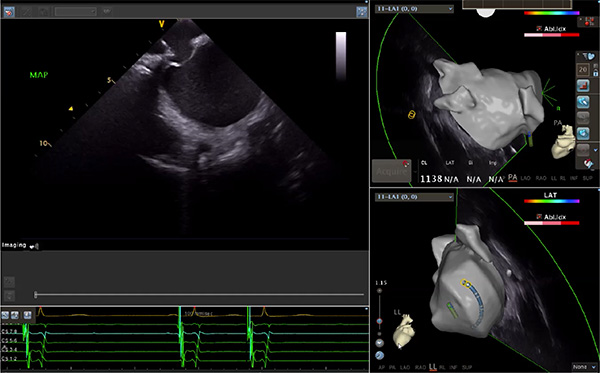

超聲心動圖技術(shù)包括常規(guī)經(jīng)胸超聲(TTE)、經(jīng)食管超聲(TEE)、心腔內(nèi)超聲(ICE)、超聲聲學(xué)造影(MCE)、三維超聲心動圖等,ICE是一種新興技術(shù)——將微型的換能器安裝在心導(dǎo)管的尖端,經(jīng)由外周血管輸送至心腔內(nèi)部,換能器發(fā)射聲波,對心臟及其鄰近組織進(jìn)行實時高質(zhì)量成像和(或)血流動力學(xué)測定的超聲成像技術(shù)?;诓煌募夹g(shù)原理,心腔內(nèi)超聲導(dǎo)管被分為兩類:機(jī)械旋轉(zhuǎn)式超聲導(dǎo)管和相控陣超聲導(dǎo)管。目前,臨床上主要應(yīng)用的是相控陣超聲導(dǎo)管,ICE成像通過術(shù)者旋轉(zhuǎn)導(dǎo)管及操縱導(dǎo)管手柄上的兩個旋鈕來完成。

ICE門檻高、集成了超聲和圖像處理最前端的技術(shù),是當(dāng)前內(nèi)窺超聲方向最挑戰(zhàn)的領(lǐng)域。不同于傳統(tǒng)接觸式三維重建方法會產(chǎn)生假腔,影響術(shù)者對靶點或結(jié)構(gòu)的判斷,心腔內(nèi)超聲(ICE)可直接顯示心臟結(jié)構(gòu),有助于理解心臟內(nèi)各部位之間的解剖關(guān)系,不僅具有實時成像、并發(fā)癥監(jiān)測以及良好的耐受性,同時以股靜脈入路,無需全麻或深度鎮(zhèn)靜,日益成為心臟介入手術(shù)中重要輔助工具,被譽(yù)為心臟介入醫(yī)生的“黃金眼”。心腔內(nèi)超聲可用于多種心臟介入手術(shù),潛在患者群體龐大,動脈網(wǎng)測算我國心腔內(nèi)超聲導(dǎo)管市場空間或?qū)⒊?00億元,具有廣闊前景。

隨著心腔內(nèi)超聲的應(yīng)用更廣,性能也在逐漸優(yōu)化,已從二維成像轉(zhuǎn)變?yōu)?strong>三維成像,極大增強(qiáng)了引導(dǎo)及可視化能力。二維心腔內(nèi)超聲支持雙平面或三平面成像,可顯示兩個或三個不同的平面視圖,但醫(yī)生需將這些圖像在腦海中重新構(gòu)建為三維解剖結(jié)構(gòu)。三維心腔內(nèi)超聲則可直接呈現(xiàn)三維解剖結(jié)構(gòu)圖,便于醫(yī)生更輕松地開展手術(shù)。按照產(chǎn)品發(fā)展方向,預(yù)計心腔內(nèi)超聲還將向更清晰、精準(zhǔn)、多功能等方向發(fā)展。